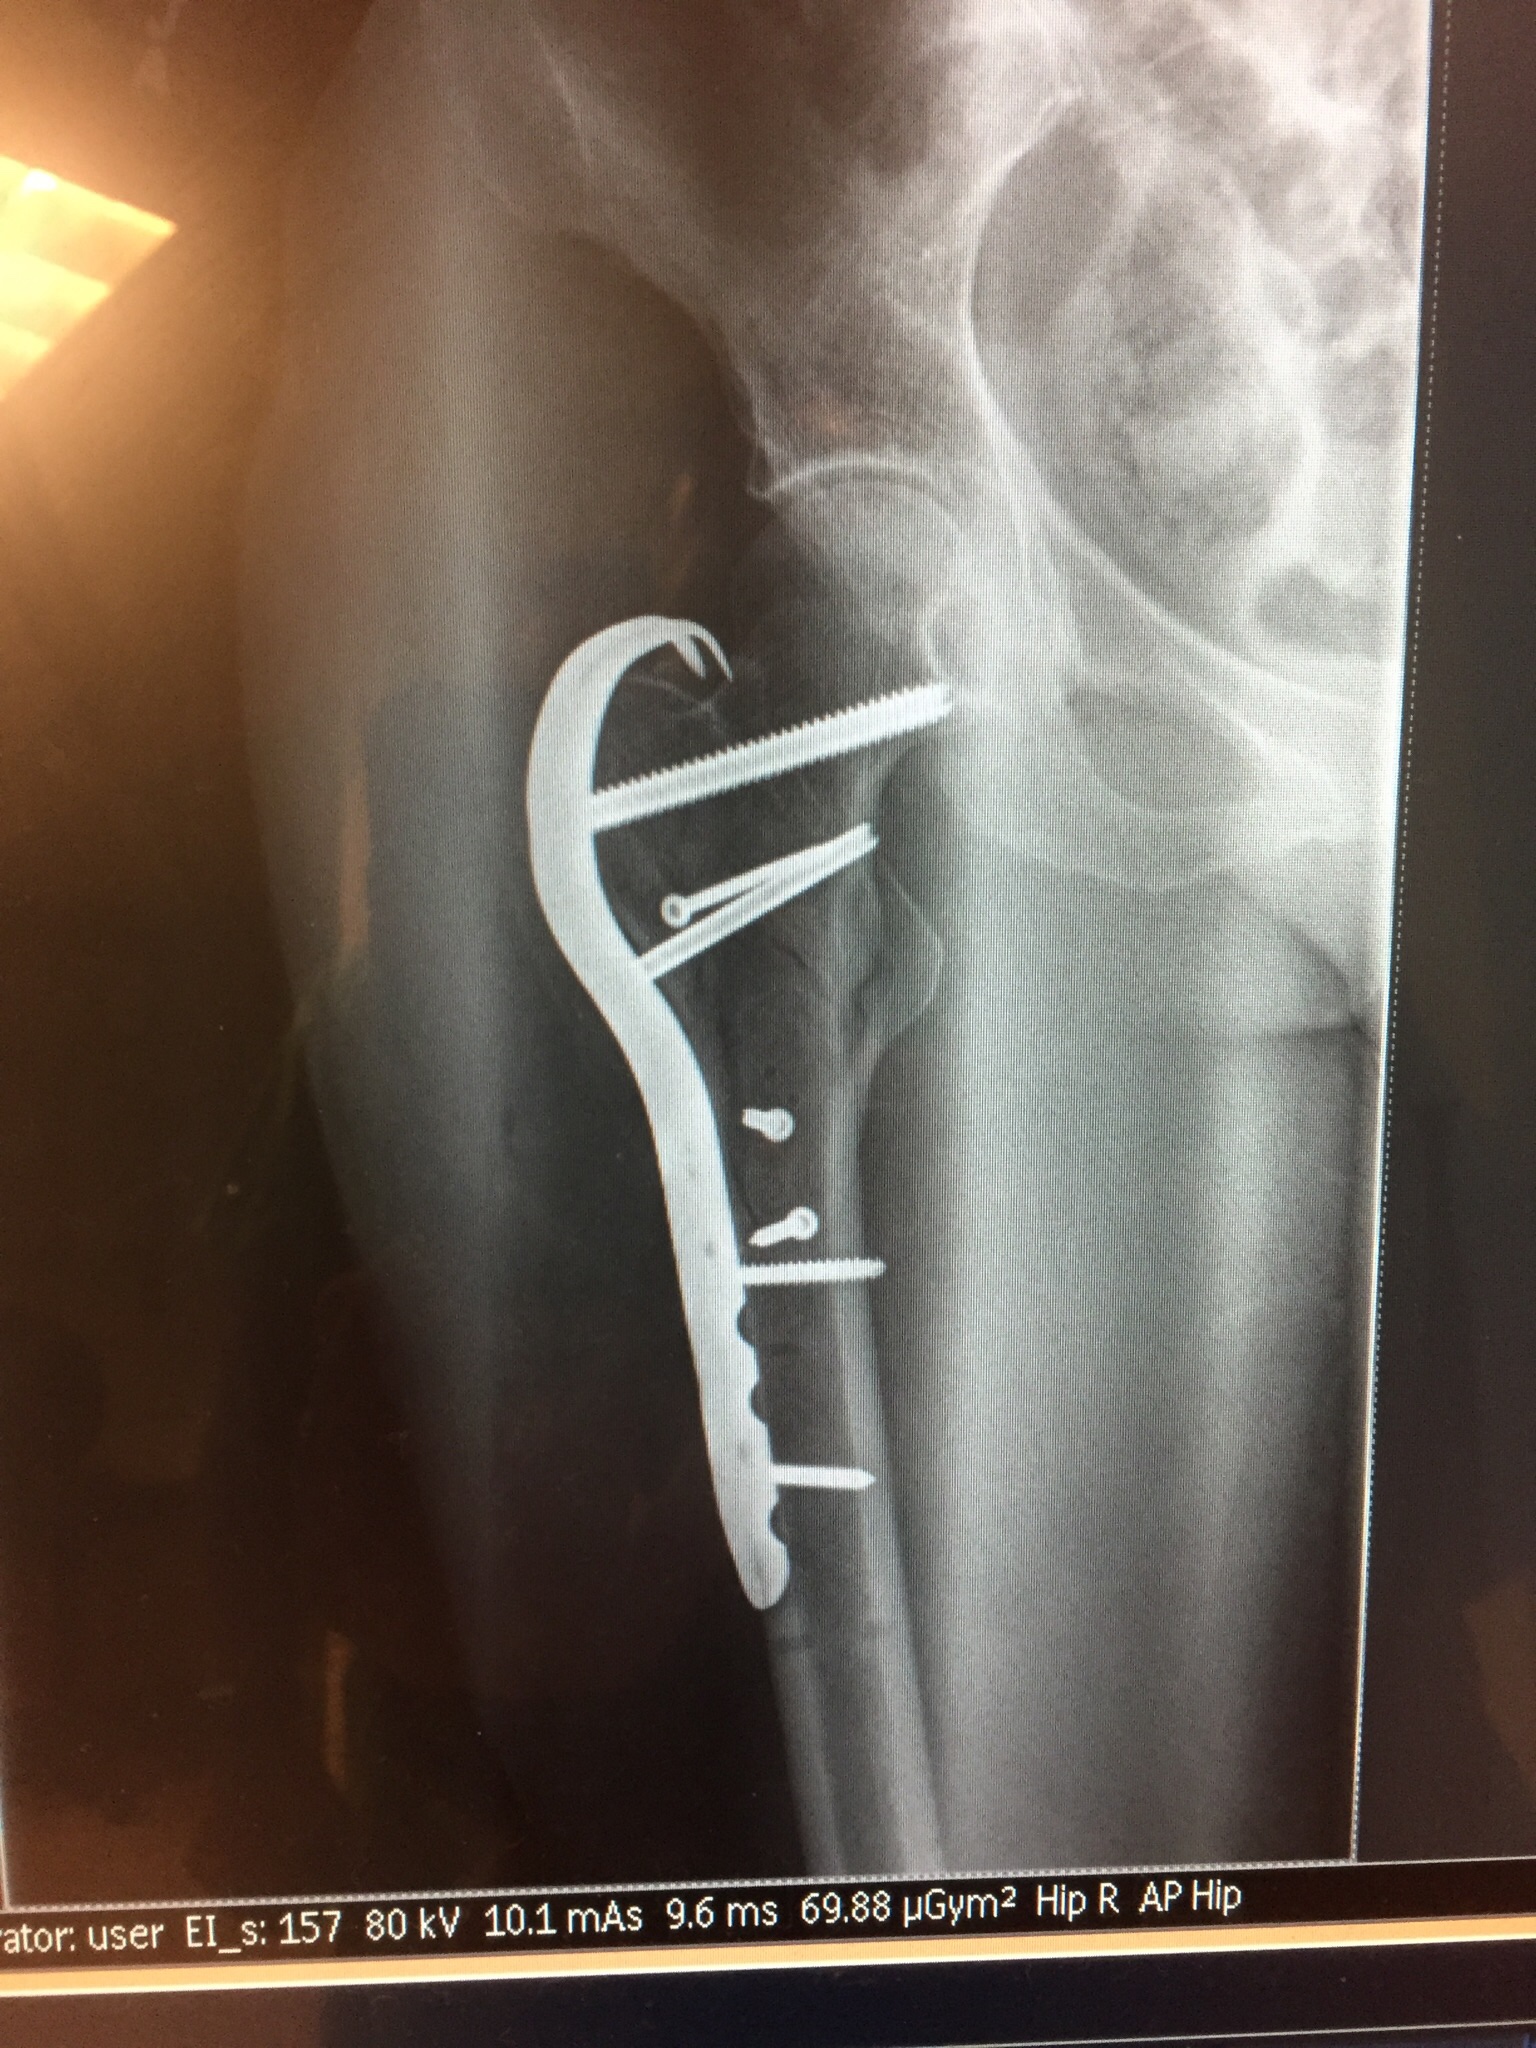

February 21, 2018, 5 AM morning walk, 33 F, Sacramento, I tripped, shattering my femur. Seven bolts, one titanium plate, 4 hours of surgery, 12 weeks no weight bearing.

The photos below show the x-ray and the actual plate, after removal. They do not, thankfully, show the 10 inch long incision, through the IT band, used to wrestle the bone fragments back to gether and install the titanium hardware. The same line of incision was reopened to remove the hardware.